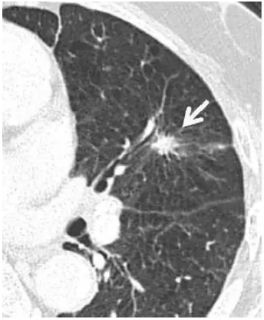

在中国人的印象里 心和肺一直是“形影不离”的 海尔兄弟 成语里有 撕心裂肺 狼心狗肺 没心没肺 …… 医学术语里有 心肺功能 心肺复苏 心肺康复 …… 尤其是当肺部查出“小阴影” 心更是脱不了关系 每天都惴惴不安 今天肿医君就来带大家看看 这让人烦恼的 肺部结节 Part.1: 肺部结节 真实病例: 张阿姨今年48岁,单位体检结果显示,肺上有一个0.8cm的小结节。张阿姨听说肺结节会变成肺癌,她担心极了,让儿子帮忙上网查询,向其他人咨询,可她得到的建议多种多样,让刘阿姨无所适从。 慢慢长大会不会变成肺癌啊 肺癌是世界上发病率及死亡率最高的恶性肿瘤,也是我国发病率和死亡率最高的疾病。目前约 75% 的肺癌患者在诊断时已属晚期,5年生存率仅为 15.6%。提高肺癌生存率的唯一途径是端口前移,早发现、早诊断和早治疗。 美国《化学文摘》2018全球癌症统计报告显示 肺癌(蓝色)高居发病率和死亡率之首 全球发病率11.6% 全球死亡率18.4% 湖南省肿瘤医院胸外一科 主任医师 陈跃军 很多患者忧心忡忡,不知道是否该进行进一步检查。如果对体检报告中的一些疾病迹象置若罔闻,等“小结节”长大变成了“肿块”,往往已错过最佳手术时机。那么我们应该怎么正确对待肺部结节呢? Part.2: 结节的分类 知识点 肺部结节(solitary pulmonary nodule,简称SPN)是肺实质完全包围的单发小病灶,类圆形或不规则形状,通常边界清晰,由肺实质包裹,不累及肺门和胸腔纵隔胸膜,不引发肺炎、肺不张或胸腔积液的组织。 肺结节分类如下 按大小: 肺结节中,直径1cm以内的称为小结节,直径0.5cm以内为微结节。局部病灶直径>3cm者称为肺肿块,也有医院将其报告为肺肿物或肺占位。 肺部结节尺寸越大,肺癌的可能性相对较大。 按数量: 肺结节可以是孤立性或多发性,孤立性肺结节即单个病灶,多无明显症状,属于边界清楚、密度增高且周围被含气肺组织包绕的软组织影。2个及以上病灶称为多发性肺结节。 肺结节的个数与肺癌可能性没有相关性 按密度: 根据病灶密度不同,肺结节还可分为实性肺结节和亚实性(非实性)肺结节,后者包括纯磨玻璃样结节。实性肺结节是肺内局限的密度增高影,病变密度相对较高,掩盖其中走行的肺细小支气管影和血管影(肺纹理);纯磨玻璃结节指CT显示的肺内密度稍增高影,通过病灶仍然能看到肺纹理影,就像透过磨玻璃观察到相对模糊的影像一样。 磨玻璃样结节尤其是持续存在的磨玻璃样结节,一般是肿瘤性病变 湖南省肿瘤医院胸外一科 主任医师 陈跃军 发现肺结节之后,不用过分紧张,但也不能掉以轻心,大部分肺结节都是良性的,只有少数肺结节是恶性的。 Part.3: 区分结节性质 结节良性的三大表现 1、 结构清晰,边缘平滑。内含脂肪和钙化的实性结节(箭头),符合错构瘤表现。建议进一步 CT 随访。 源自美国Fleischner 学会2017 年公布案例图(下同) 2、 有明显钙化痕迹。CT 图像显示边界清楚的中心钙化(a)或层状钙化(b)结节,均为典型的肉芽肿表现。建议进一步 CT 随访。 3、没有变大的趋势,甚至逐渐消失。(a)左肺上叶层厚 1 mm 的 CT 横断面图像,显示一个模糊的 10 mm 大小磨玻璃样结节(箭头)。(b)4 个月后的 CT 随访图像,显示未经治疗的病变在随访间期消失,符合良性病因,如局灶性感染。 结节恶性的三大表现 1、 毛刺状结节 左肺上叶层厚 1 mm 的 CT 横断面图像,显示一个可疑的实性毛刺状结节(箭头)。手术证实为浸润性腺癌。 2、 磨玻璃区域逐渐长大的结节 (a)右肺中部层厚 1 mm 的 CT 横断面图像,显示一个 10 mm 大小的纯磨玻璃样结节(箭头)。(b)同一位置 15 个月后的 CT 随访图像,显示病变的不透明度只有很小增加。(c)取得 b 图 10 个月后,同一位置的 CT 图像,显示结节已发展成较大的实性结节。手术切除证实为 1A 期浸润性鳞屑样为主的腺癌 3、实性结节逐渐变大的结节 (a)右肺下叶上段层厚 1 mm 的 CT 横断面图像,显示一个高度可疑(较大、磨玻璃样外观和实性形态)的部分实性结节(箭头)。(b)3 个月后的 CT 随访图像显示,实性成分的大小逐渐增加。手术显示为浸润性腺癌。 除了上述影像资料,咨询者的生活方式也是判断依据。 肺癌的高危人群 (1)年龄在55岁以上; (2)年数乘以每天吸烟的支数>400支*年的吸烟患者,其中也包括曾经吸烟,但戒烟时间不足15年者;被动吸烟者; (3)有职业暴露史(石棉、铍、铀、氡等接触者); (4)有恶性肿瘤病史或肺癌家族史; (5)有慢性阻塞性肺疾病(COPD)或弥漫性肺纤维化病史。 Part.4: 发现结节怎么做? 1、肺部小结节并不等于肺癌,并且大部分是良性的,有的通过保守治疗如抗炎或抗痨治疗,甚至不做任何治疗观察后消失。因为人体有自身免疫力的,只要营养好,一般的炎性病变可自行吸收。 2、当医生判断结节恶性可能性较小时,还是建议患者要定期检查胸部CT。5毫米以下的微结节每年复查一次,5至10毫米的小结节每三个月复查一次,随访三至五年。 CT在肺内病变中的诊断优势非常明显,CT通过显示组织横断面及三维结构图像进行诊查,有效避免了肺与心脏、纵隔、横膈等组织的重叠,能发现肺尖、脊柱旁、靠近胸膜、心脏后方等部位胸片难以发现的病灶。另外,低剂量CT筛查所产生的射线剂量很低,对人体的影响极低。 3、当医生判断为恶性可能性较大时,应早期进行手术(胸腔镜)治疗。国内外多个研究结果显示,经过手术治疗的I期患者的10年生存率达到了90%以上。 目前微创胸腔镜手术是治疗肺部小结节、早期肺癌的主要方法。胸腔镜手术应用广泛,只需一个1cm胸腔镜观察孔和一个2-3cm操作孔,行肺叶或肺段切除术,疗效明确,创伤非常小,疼痛轻,术后恢复快,不需要做任何的化疗和放疗。 在我们临床工作中对上千例磨玻璃结节、微小结节患者的长期临床观察研究结果显示,90%以上患者的结节没有发生变化,10%的患者在随访过程中发现结节长大或实质成分增加等改变,及时手术,但没有一例出现复发转移,所以只要找对了专家,定期随访,并不会耽误治疗。 最危险的情况其实是病人发现肺部结节去看医生,医生考虑肺部小结节可暂时不处理,建议定期复查,而病人把不手术、不服药误认为没病,一直拖到出现症状后再去就诊,耽误了病情。